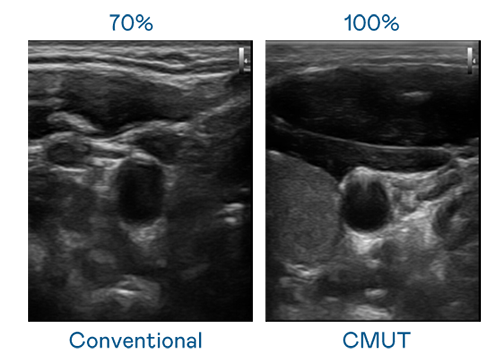

CMUT 技術是一種用電容式微機電元件來產生超音波訊號的技術。與傳統 PZT 壓電式技術相比,CMUT 頻寬增加 30%,更寬頻的超音波訊號讓影像解析度大幅提升,是實現高影像品質醫療超音波掃描、促進精準醫療發展的關鍵技術。

大頻寬帶來超清晰影像

超音波影像的解析度高低,首先取決於探頭能發出的訊號頻寬。华体汇官网登录入口 CMUT 可提供高清晰的超音波訊號,提供高頻寬、高靈敏度、影像紋理細節更高的超音波影像,協助醫護人員縮短影像判讀時間及利用精準的醫療影像進行診斷。